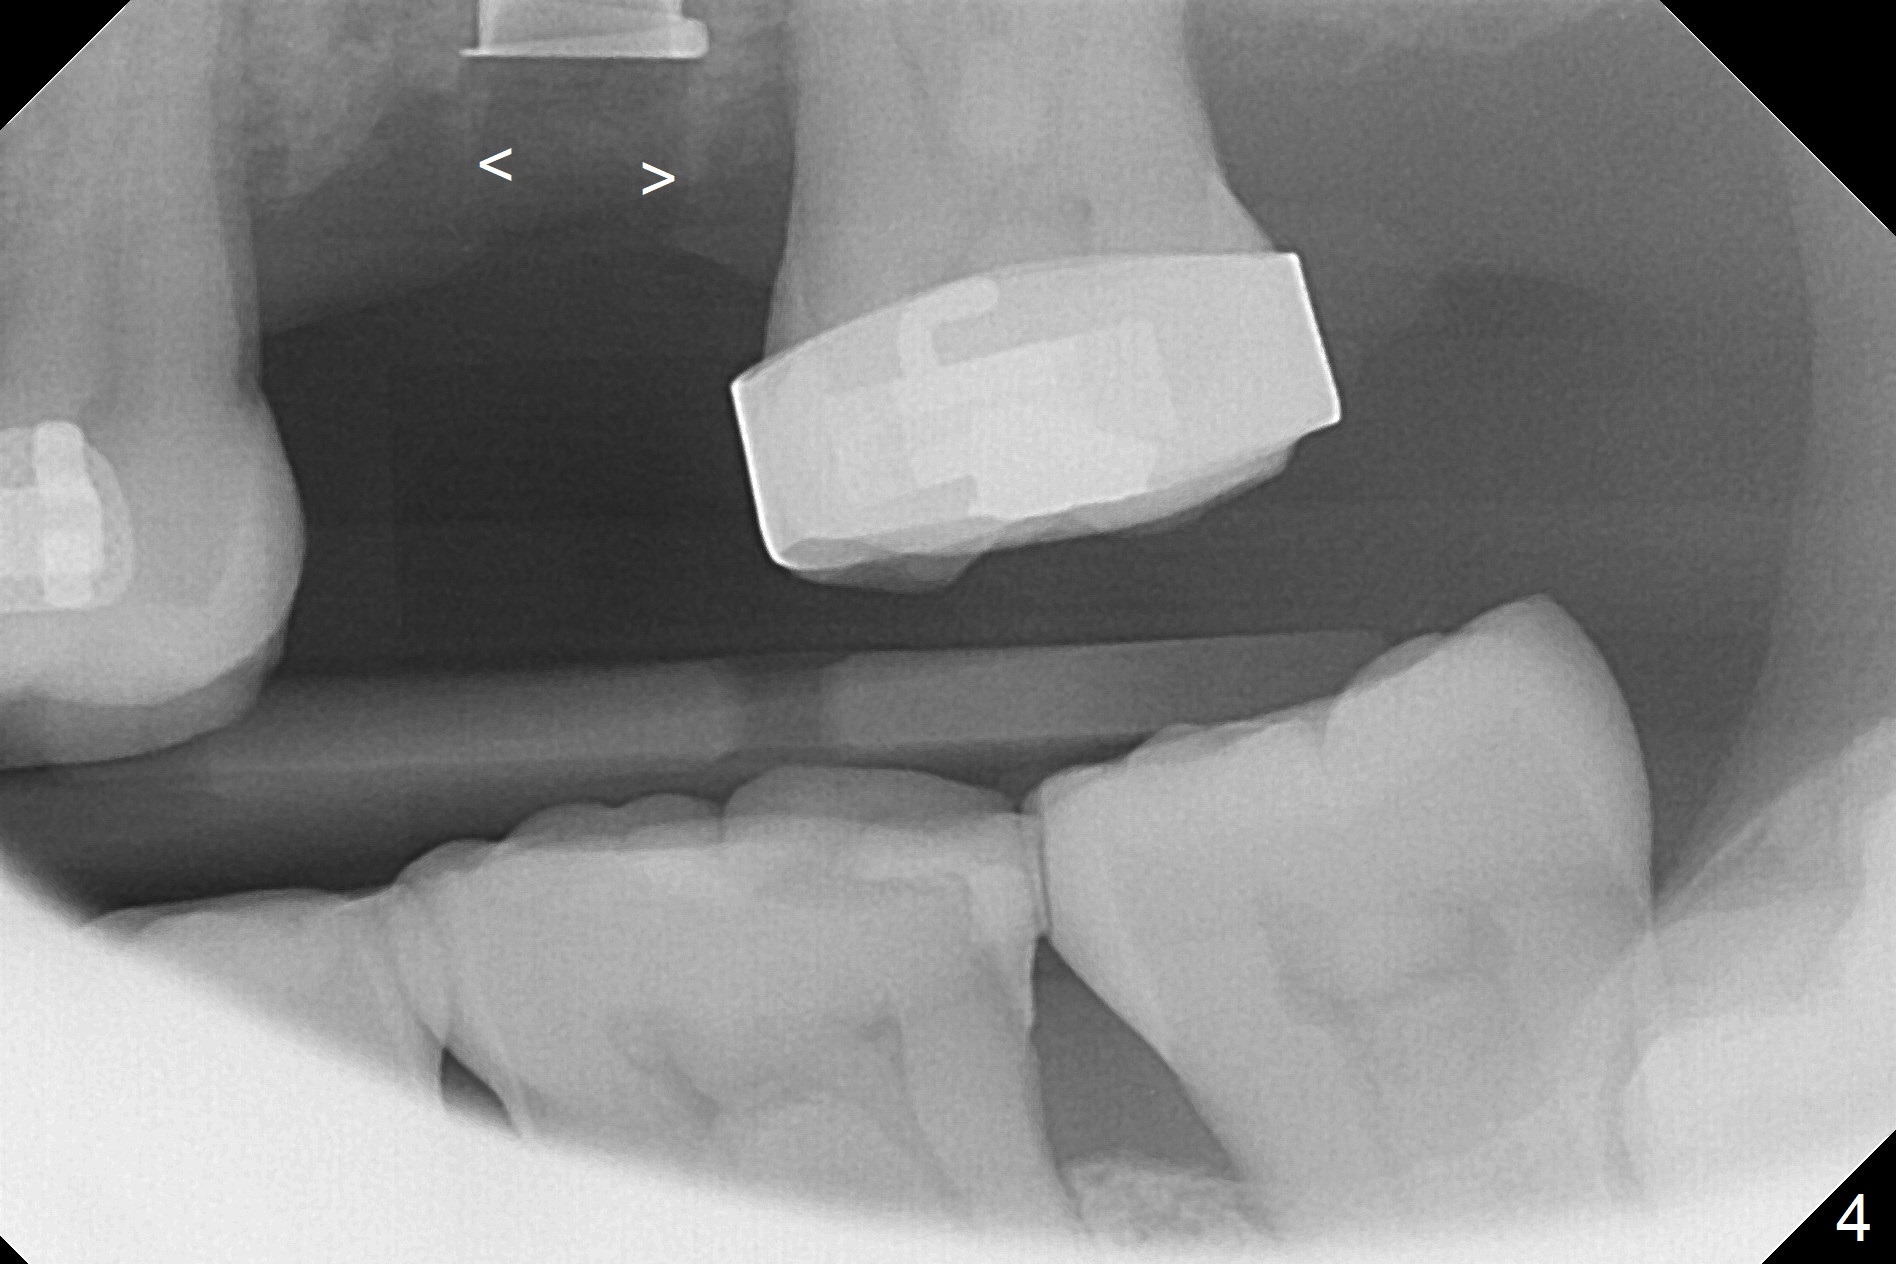

Preop exam shows the narrow ridge at #14. Magic split is used for access and initiation of osteotomy and bone expansion, followed by 3 mm Magic Expander for 11 mm (ME, Fig.1 (yellow line: sinus floor)). In fact the bone is soft. After use of 3.8 mm ME and Lindamann bur (to move the osteotomy distobuccally), a 4x11 mm dummy implant is placed with 20 Ncm (Fig.2). Following use of Lindamann bur for the same purpose as mentioned above, a 4.5x9 mm IBS implant is placed 3 mm subgingival with <30 Ncm (Fig.3,4). Bone graft is placed for sinus lift prior to implantation. A 5x3 mm healing abutment is placed. Bone loss is minimal 3.5 months postop (Fig.5) and striking 8 months postop (after crown cementation, Fig.6-8). The bone loss persists in spite of crown and abutment removal (Fig.9,10). Bone graft or implant redo is planned.